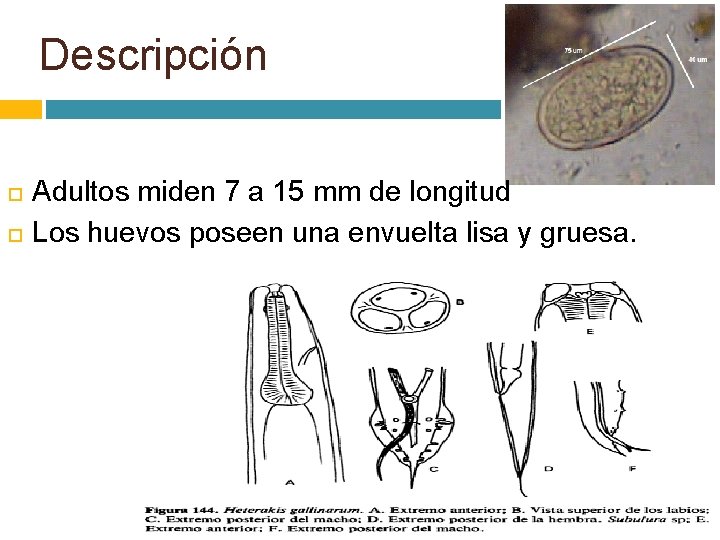

Descripción Adultos miden 7 a 15 mm de longitud Los huevos poseen una envuelta lisa y gruesa.

Biología y ciclo vital directo. Las hembras depositan hasta 900 huevos al día que llegan al exterior con las heces